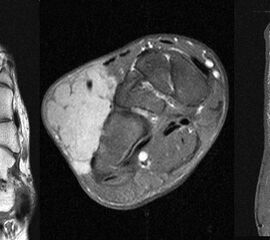

MR-tomographische Darstellung eines unspezifischen weichteiligen Raumforderug im Bereich des dorso-lateralen Rückfußes. Die offene Probebiopsie ergab schließlich die Diagnose eines hochmalignen Synovialsarkoms.

Abbildung 34